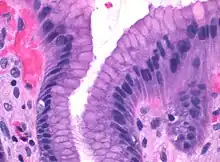

Microscopic section of gastric mucosa. Foveolar cells can be seen at top of the image lining the surface and pits

Foveolar cells or surface mucous[1][lower-alpha 1] cells are mucus-producing cells which cover the inside of the stomach, protecting it from the corrosive nature of gastric acid. These cells line the gastric mucosa (mucous neck cells are found in the necks of the gastric pits). The mucus-secreting cells of the stomach can be distinguished histologically from the intestinal goblet cells, another type of mucus-secreting cell.

Foveolar cells line the surface of the stomach, the gastric pits, and the top part of gastric glands: the neck. They constitute a simple columnar epithelium, as they form a single layer of cells and are taller than their width. Depending on their location, foveolar cells can be divided in two groups: surface mucous cells, which line the surface and the gastric pits; and mucous neck cells, which are a part of the neck of gastric glands along parietal cells.[2]:257

Surface mucous cells have large quantities of mucin granules in their apical (top) surface and project short microvilli into the lumen of the stomach.[2]:257 Mucins are large glycoproteins that give the mucus its gel-like properties.[3] As mucins are lost during routine histology preparation, they stain pale, but if preserved correctly the cells stain strongly with special techniques like PAS or toluidine blue, the last representing the anionic nature of foveolar cell secretions. Below the mucin granules, surface mucous cells have a Golgi apparatus, the nucleus, and small amounts of rough endoplasmic reticulum.[4]:577 Mucous neck cells are located within gastric glands, interspersed between parietal cells. These are shorter than their surface counterpart and contain lesser quantities of mucin granules in their apical surface.[4]:578